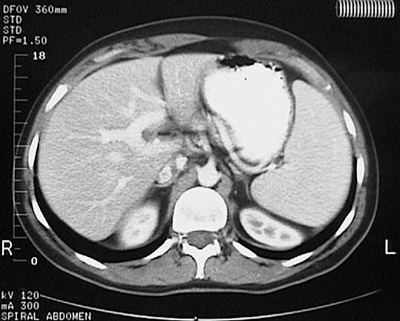

Here is another example of

splenomegaly

as seen with an abdominal CT scan. In this view, the spleen is quite large and extends down to the level of the

kidneys

.